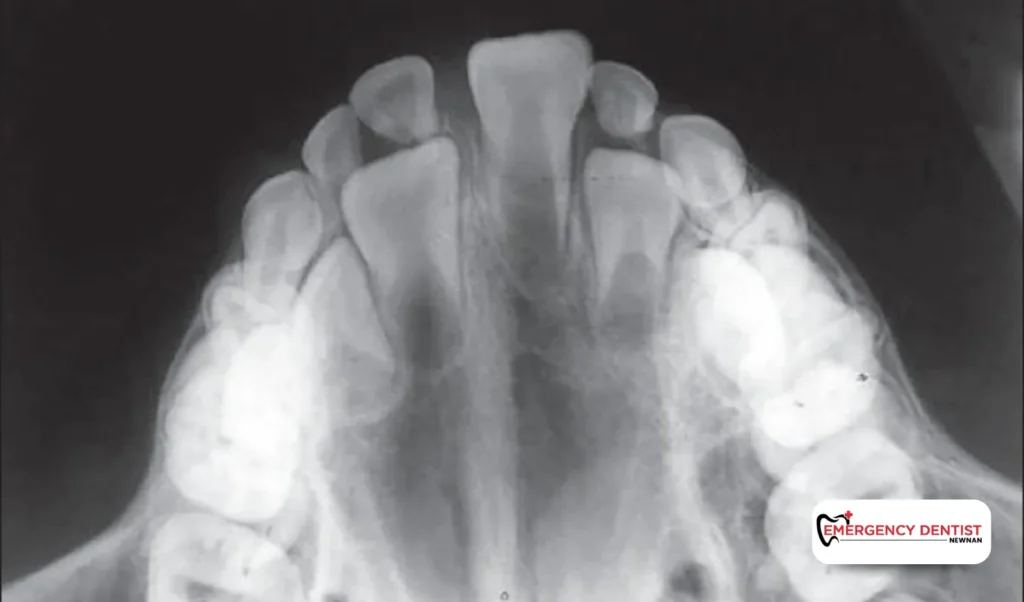

• Occlusal X-rays: Provide larger images of the jaw and palate, often used in children or when investigating unusual growths.

• Panoramic X-rays: Offer a complete view of the jaws, teeth, and sinuses. Often used for orthodontic treatment, wisdom tooth removal, or to spot hidden issues.